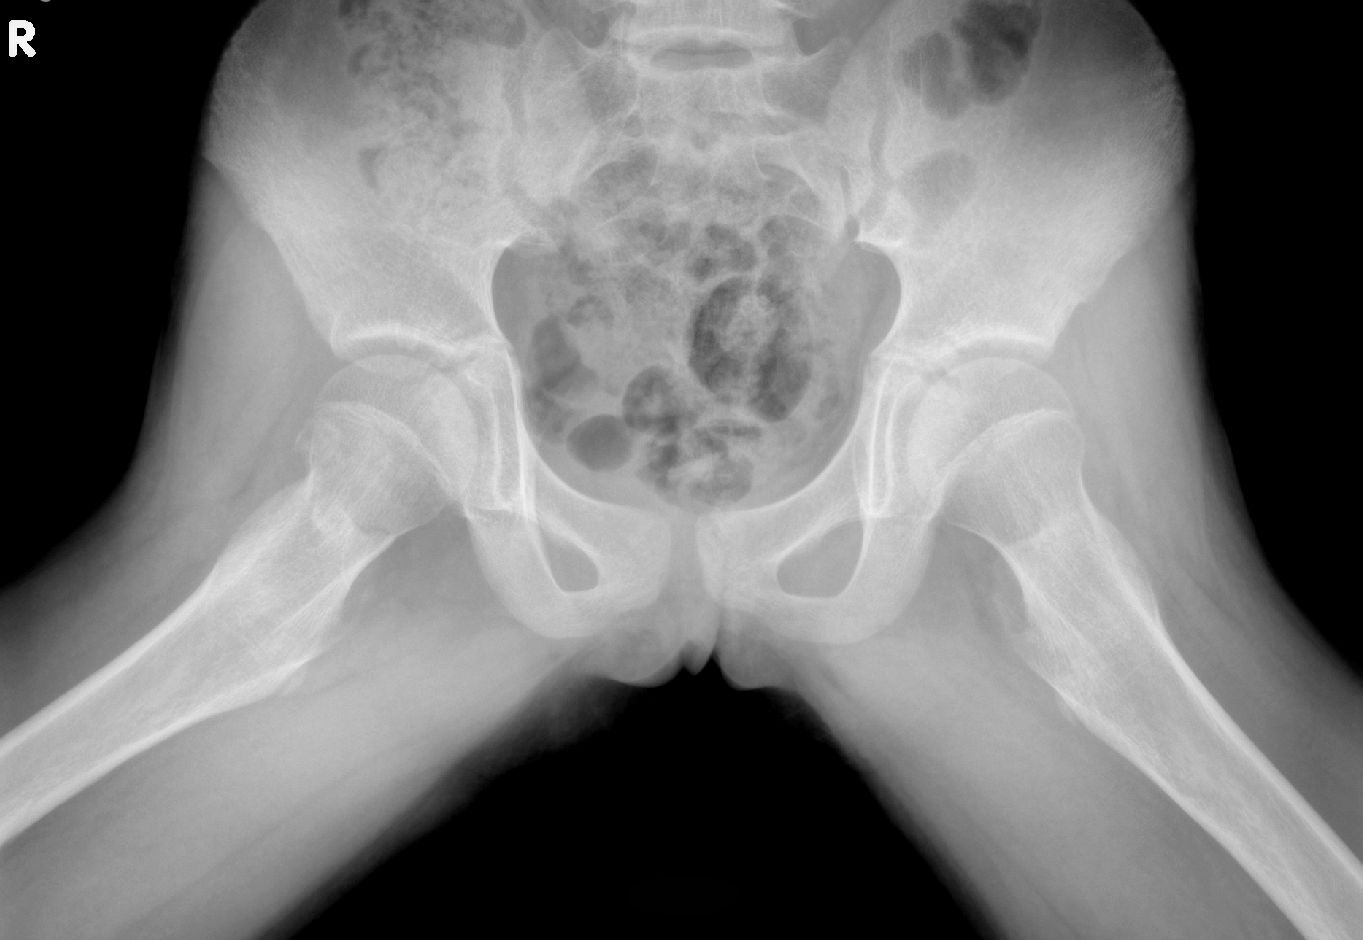

标题: X5929:右股骨颈骨折吗?

右股骨颈似有透亮裂隙影,无明显移位征象;考虑右股骨颈骨折可能,建议ct检查。

正位示股骨颈可见不规则稍致密线状影,蛙氏位可见皮质不连。考虑右股骨颈骨折。

下肯定诊断:右股骨颈骨折。

蛙式位右侧股骨颈有线形透亮影与大粗隆重叠无关,近骺端还可见多出一块呢,支持骨折。

支持骨折!正位片上右股骨颈缩短,颈中部密度增高,是软组织重叠还是骨折后,骨干外旋造成的骨质重叠?结合蛙式位的透光线,应该是骨折!

有外伤病史,考虑嵌插性骨折。

此小孩做了ct ,未见明显骨折线,但右股骨头外有骨块影,不知何解。

本人认定是骨折。

支持考虑右股骨颈头下型骨折。ct扫描没发现异常与扫描角度及层后都有关。